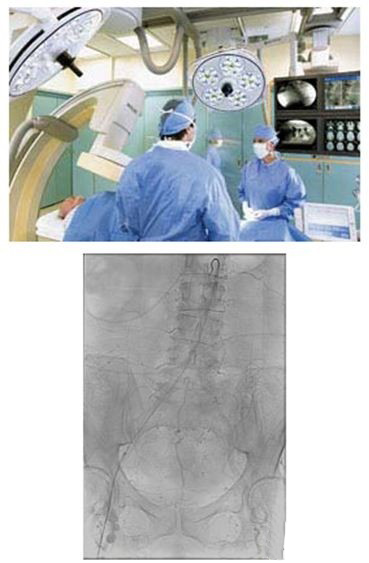

當(dāng)患者在躺手術(shù)臺上,介入放射學(xué)醫(yī)師會引導(dǎo)導(dǎo)管運(yùn)動,通過一系列錯綜復(fù)雜的動脈血管。當(dāng)醫(yī)師引導(dǎo)導(dǎo)管通過動脈網(wǎng)到達(dá)冠狀動脈和所關(guān)注的區(qū)域時,醫(yī)師可從顯示器上得到實時反饋,從而小心地移動導(dǎo)管進(jìn)行介入治療。

如果沒有適當(dāng)?shù)囊龑?dǎo)來通過狹窄彎曲的通路,醫(yī)生則必須完全開胸,除此之外沒有其他選擇,而開胸手術(shù)會增加患者風(fēng)險、延長恢復(fù)時間并會增加手術(shù)費(fèi)用。介入放射學(xué)的進(jìn)展使得內(nèi)部結(jié)構(gòu)的圖像得以改進(jìn),使得醫(yī)生能夠?qū)嵤┪?chuàng)手術(shù),從而降低衛(wèi)生保健支出,并盡可能減少患者創(chuàng)傷。

大量手術(shù)都屬于介入類別,包括在動脈、靜脈、淋巴或膽管系統(tǒng)利用血管成形術(shù)放置導(dǎo)管、放置血管支架、進(jìn)行導(dǎo)管栓塞、血栓溶解和化療或?qū)Ыz栓塞。臨床醫(yī)生在診斷和治療心血管疾病和腫瘤方面發(fā)現(xiàn)了利用介入放射學(xué)的重大機(jī)遇。無論他們利用血管成形術(shù)或放置支架來開放閉塞的冠狀動脈,還是進(jìn)行化療栓塞來阻斷腫瘤的血流,介入學(xué)醫(yī)師進(jìn)行的手術(shù)越來越多,預(yù)期介入手術(shù)的增多在未來會一直持續(xù)下去。大量因素刺激了這一增長,包括老年人群的增多,以及通過微創(chuàng)的定向治療來降低治療難度和減少患者創(chuàng)傷的需要。這一方法可使患者治療效果更好、住院時間縮短,并最終降低醫(yī)療支出。